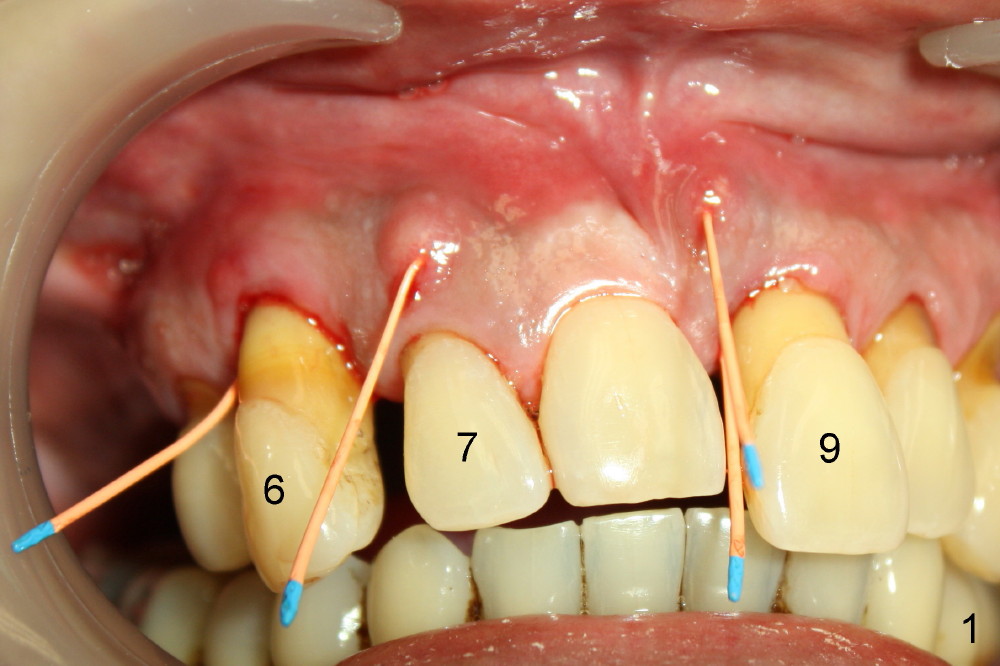

A 52-year-old man has severe periodontal disease (Fig.1-3). It appears that the upper teeth are non salvageable and are best treated by hybrid denture. But his finance is strained.

The most severely affected teeth (#6,7 and 9) are extracted and immediately replaced by 4x20 mm (#7) and 5x20 (#6,9) implants (Fig.4,5). Straight (0 degree) uniposts (3 and 4 mm, respectively) are rotated tightly into the wells of the implants by hand screw driver. In order to have reversibility to hybrid denture in the future, these uniposts are not cemented. Heavy retention grooves are placed between the uniposts and implants. Provisionals are fabricated immediately and cemented temporarily. To increase stability, flowable composite is added to the area between the provisionals of #6 and 7.

Fig.6 shows these provisionals 1 week postop. The patient is happy with the result. His diet is confined to soft food. The provisional at the site of #9 is slightly mobile.

Tomorrow (1.5 months postop) the patient will return because of a loose temporary crown. What should I do? Retighten the loose unipost or permanently cement it?

When fabricating definitive crowns, can we afford not to cement the uniposts so that convertibility into hybrid denture is possible?